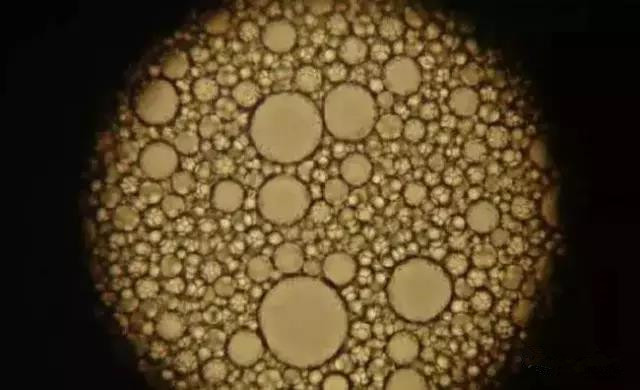

“ 镜下脂肪滴

“ 正常鲤鱼肝胰脏

鱼的肝脏两种类型:

1、肝细胞内含糖原为主。光鳃鱼、冰?等。2、肝细胞内含脂肪为主。河?、黄盖鲽等,天生脂肪肝。脂肪肝的原因:饲料原因 :养殖鱼类约90%以上有脂肪肝。